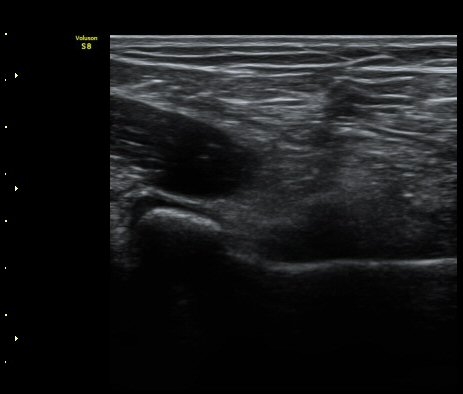

ÆÈ²ÞÄ¡  ¾ÕÂÊ¿¡¼­ ½ÃÇàÇÑ ¿ä°ñµÎ Á¾´Ü¸é°Ë»ç¿¡¼­ ƯÀÌ ¼Ò°ßÀ» º¸ÀÌÁö ¾ÊÀ½(±×¸² 1).